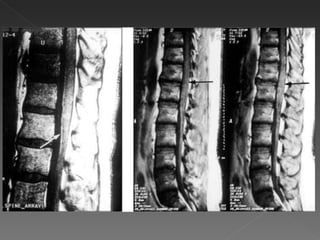

Tumefação variável da medula espinhal. Áreas difusas ou multifocais de sinal brilhante anormal em sequências pesadas em T2, podendo se estender por vários segmentos da medula espinhal. Nos casos agudos, pode se observar captação de contraste, indicativa  de ruptura da barreira hematencefálica associada a inflamação perivenosa. Também exclui compressão de medula.

Tumefação variável damedula espinhal. Áreas difusas ou multifocais de sinal brilhante anormal em sequências pesadas em T2, podendo se estender por vários segmentos da medula espinhal. Nos casos agudos, pode se observar captação de contraste, indicativa de ruptura da barreira hematencefálica associada a inflamação perivenosa. Também exclui compressão de medula.